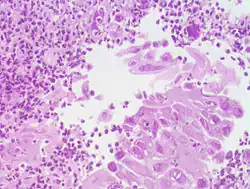

Морфологические формы эзофагита

| Катаральная форма | Характеризуется гиперемией и отёчностью слизистой оболочки пищевода. Наиболее распространённая форма эзофагита. |

| Отёчная форма | Характеризуется гиперемией и отёчностью слизистой оболочки пищевода. Наиболее распространённая форма эзофагита. |

| Эрозивная форма | Чаще всего развивается при острых инфекционных болезнях и действии на стенку пищевода раздражающих веществ. |

| Геморрагическая форма | Развивается при некоторых инфекционных и вирусных болезнях (например, при сыпном эпидемическом тифе, гриппе). |

| Псевдомембранозная форма | Наблюдается при дифтерии, скарлатине. При этой форме фибринозный экссудат не спаян с подлежащими тканями. |

| Эксфолиативная форма | Наблюдается при дифтерии, скарлатине. При этой форме фибринозный экссудат прочно связан с подлежащими тканями. |

| Некротическая форма | Встречается при тяжёлом течении инфекционных болезней, таких, как корь, скарлатина, брюшной тиф и др., а также при кандидозе, агранулоцитозе, сопровождается образованием глубоких язв. |

| Флегмонозная форма | Образуется в результате внедрения в стенку пищевода инфицированного инородного тела, процесс может распространиться вдоль пищевода и в сторону средостения. |